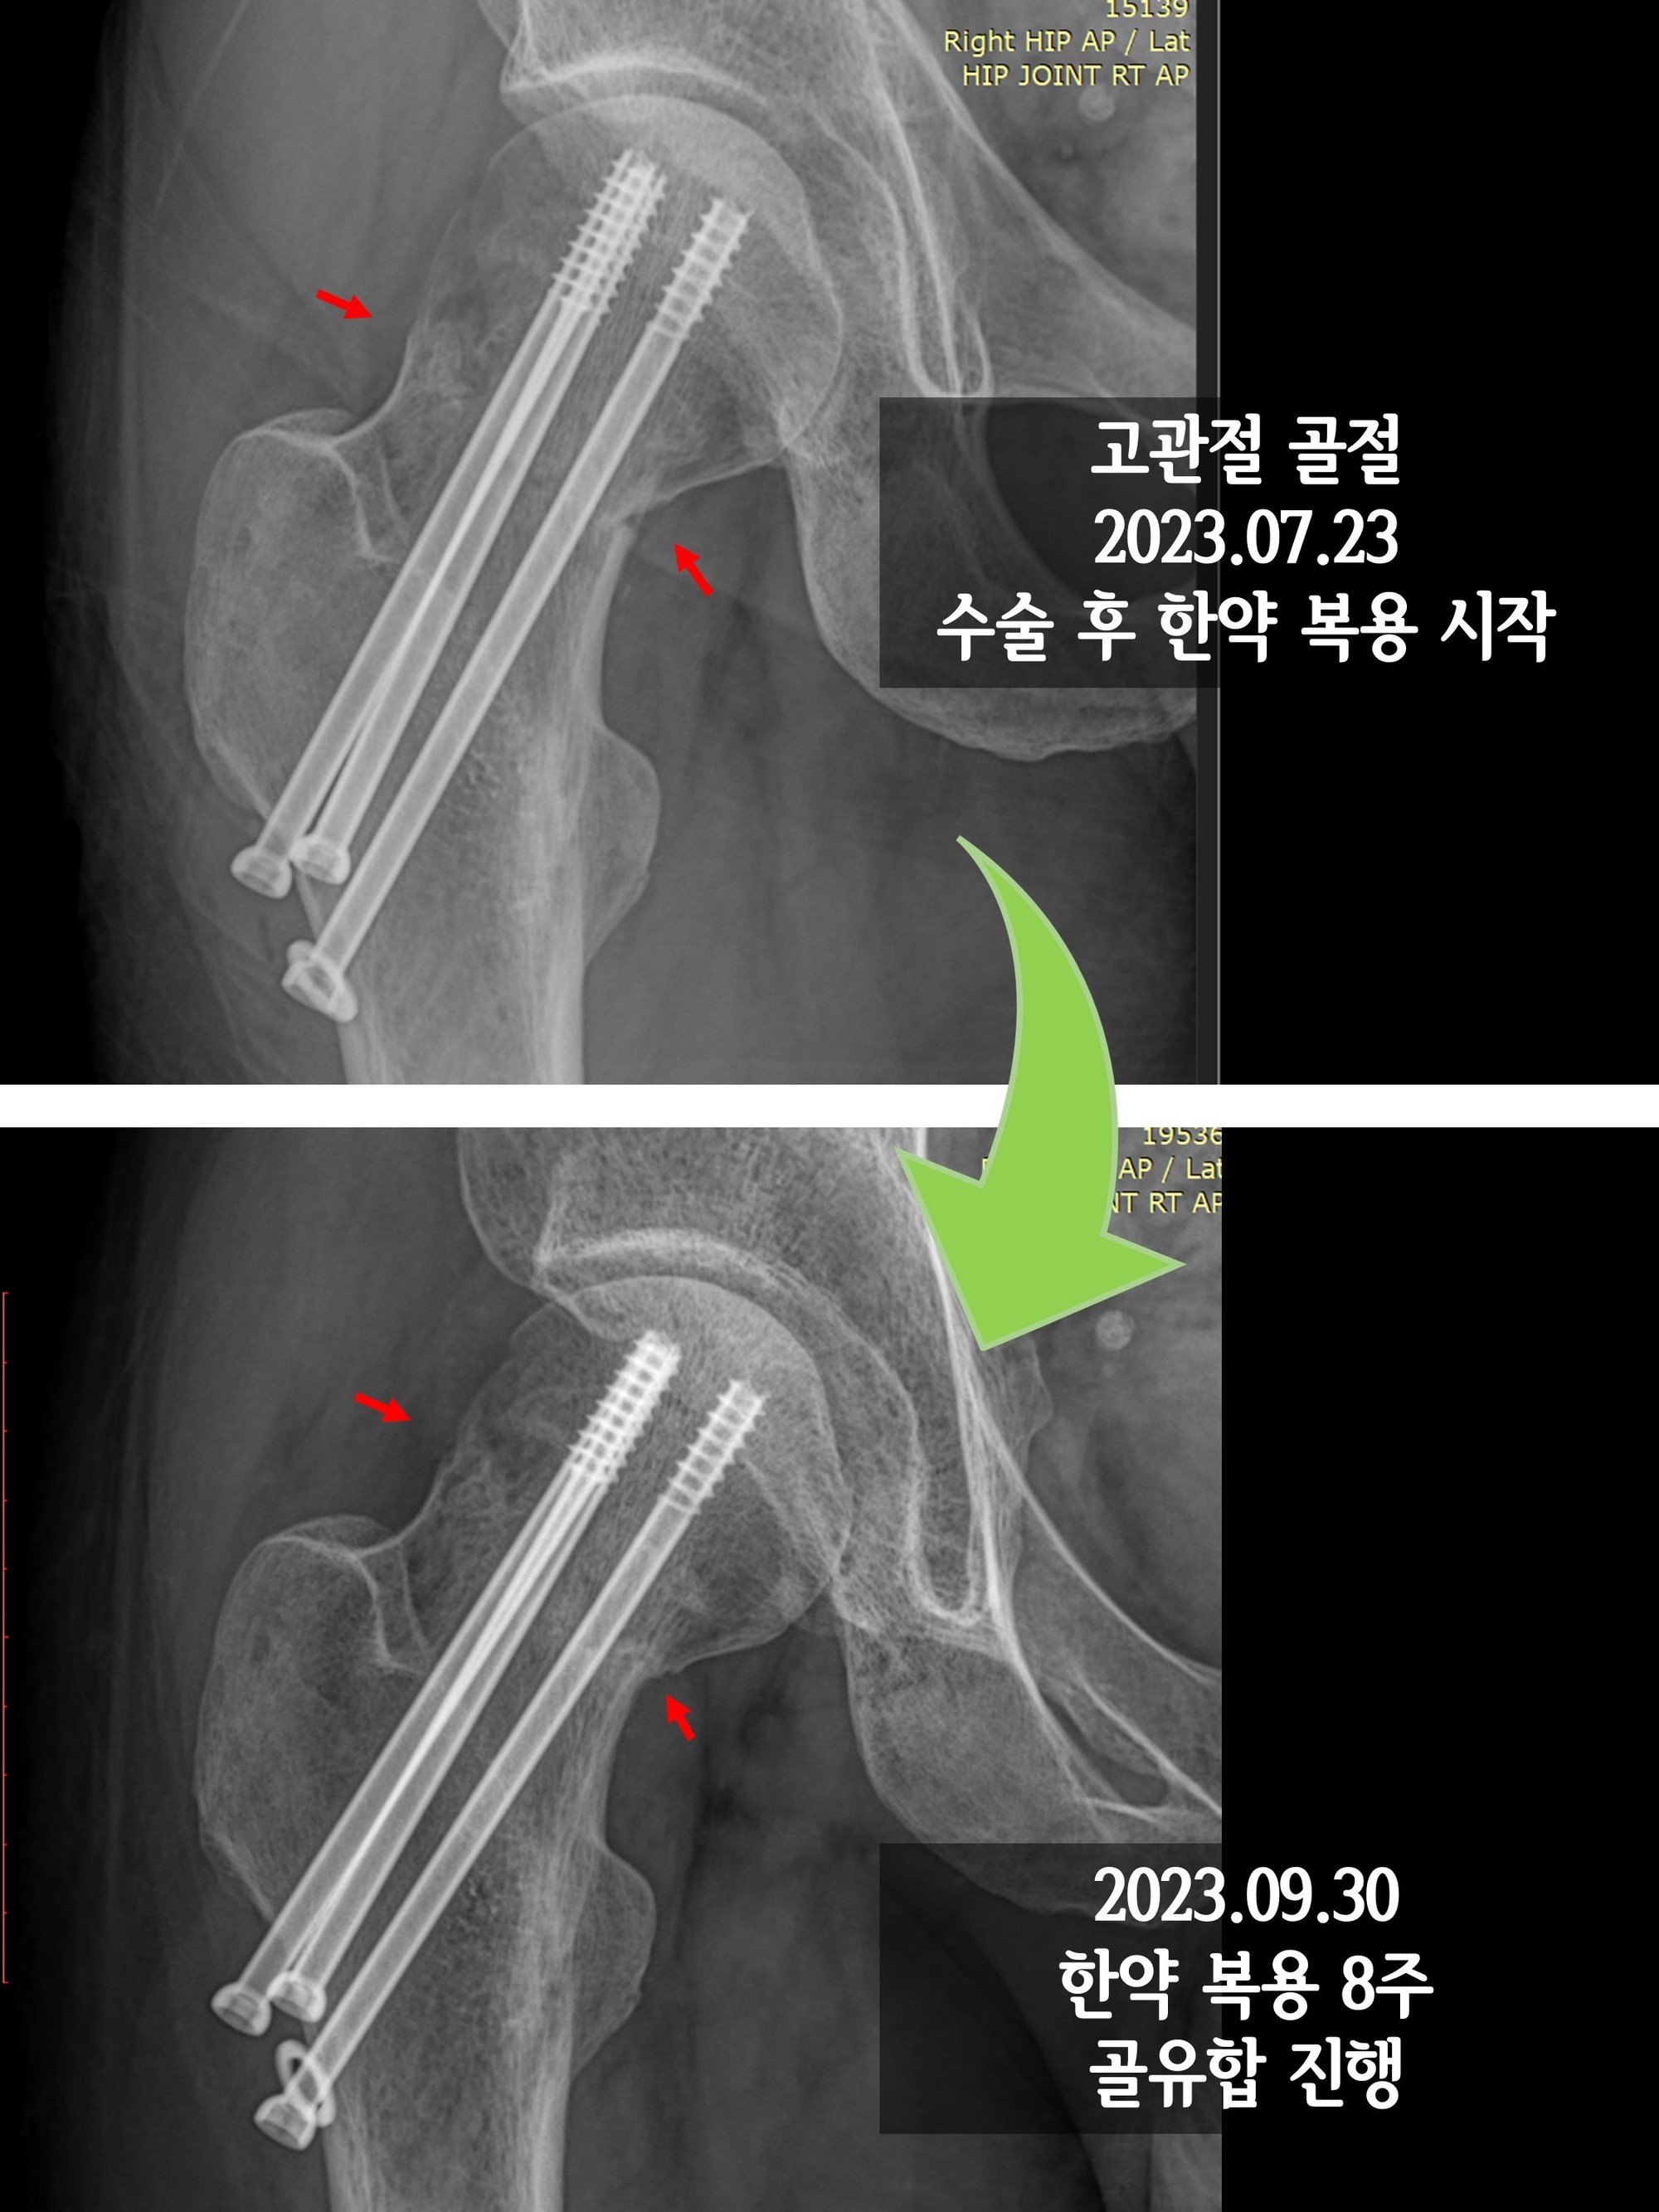

- 진단적 검사: 의사가 필요할 경우 정기적으로 X-ray나 MRI를 통해 관절의 상태를 체크할 수 있습니다.